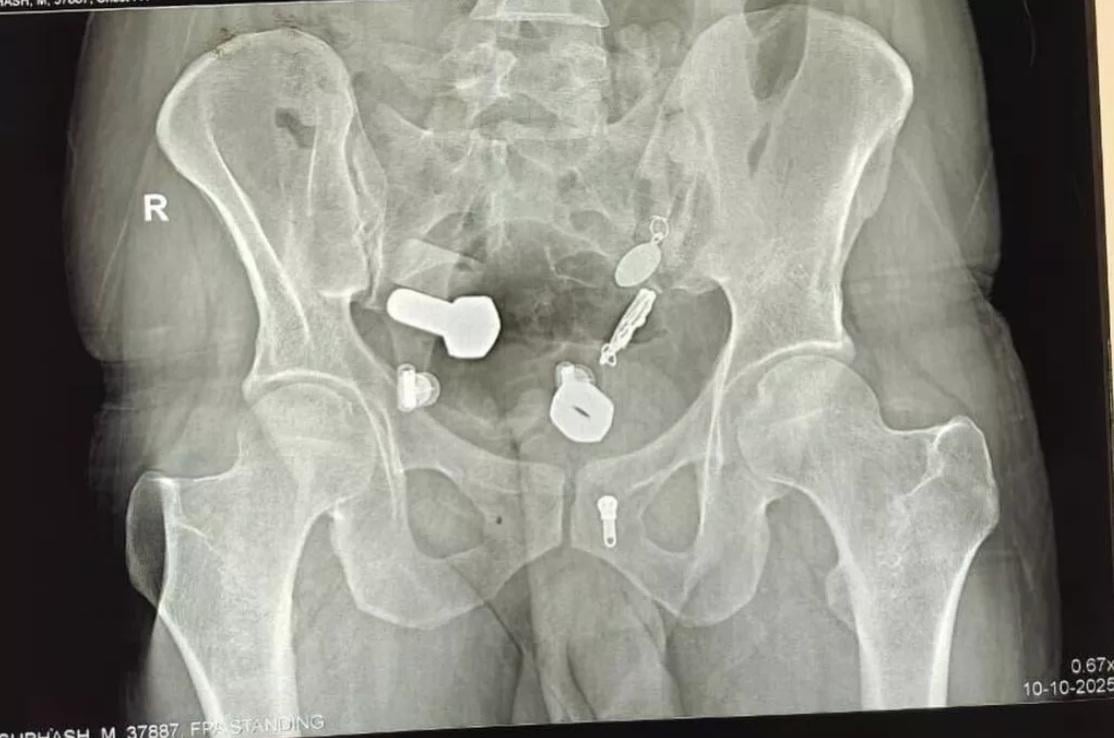

又一異食癖的誇張案例……英國《鏡報》等媒體報道,印度齋浦爾(Jaipur)一名34歲男子因劇烈腹痛、無法飲水進食,本月9日被家人送往醫院急症室就診。醫生替他做X光等檢查,驚見他食道裡竟卡著一隻手錶,大腸裡還有多塊鐵片、螺絲帽、螺絲、繩子、吊墜等物品,讓醫療團隊十分驚訝。

手術過程被拍下,醫生從男子腹部的小切口拉出手錶。(互聯網) X光檢查發現,男子腸道裡有鐵片、螺絲帽、螺絲等異物。(互聯網) 醫生從男子的食道和腸道取出手錶、鐵片、螺絲帽、螺絲和繩子等異物。(互聯網) X光檢查發現,男子有手錶卡著食道,腸道裡有鐵片、螺絲帽、螺絲等異物。(互聯網)